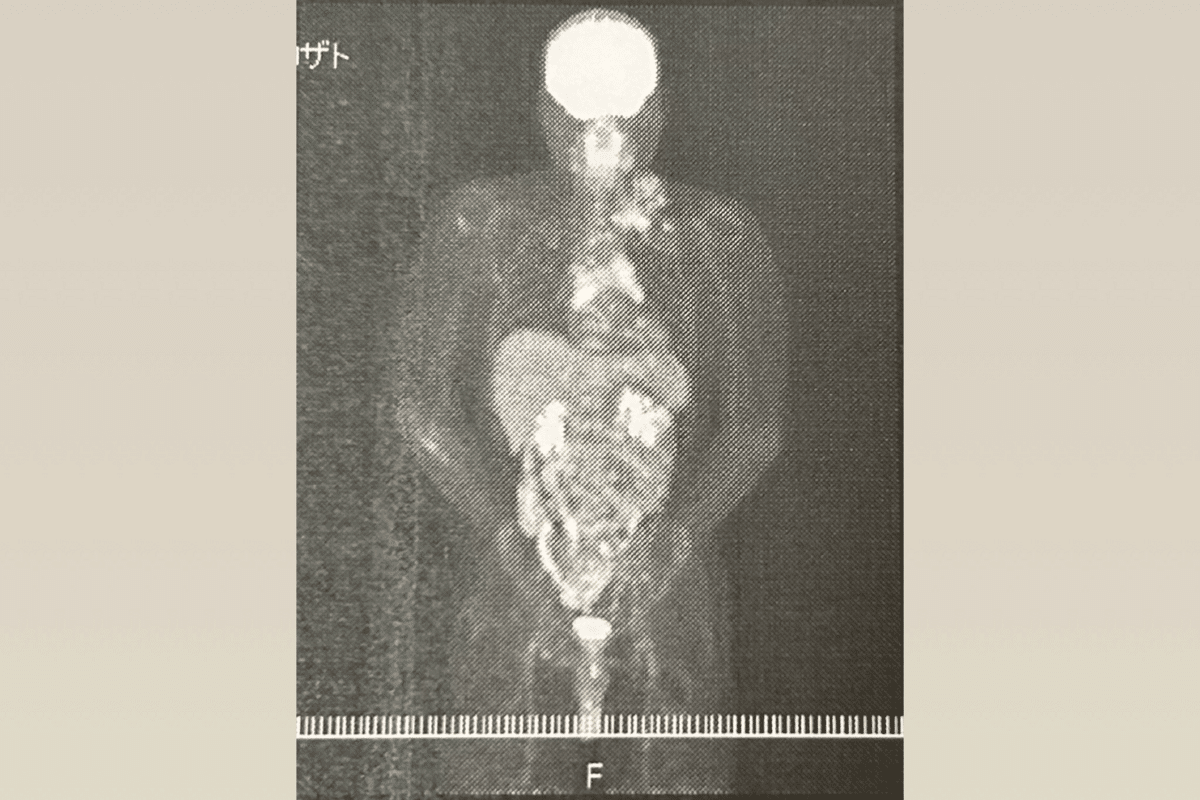

病院に到着し、先生から告げられたのは悪性リンパ腫(Tリンパ芽球性リンパ腫)という病名でした。この病気は進行がとても早く、治療をしなければ3ヶ月もたないということでその日に緊急入院という運びに。予想していたとはいえ、いざ告げられると頭が真っ白になり、涙が止まりませんでした。親に心配をかけまいと、ひとしきりトイレで泣いた後、電話で親に病気のことを伝えました。

この日からは私の日常は一変しました。まず、1週間のステロイドパルス療法を行った後、辛い抗がん剤治療が始まりました。抗がん剤治療の副作用で髪の毛は抜けていき、強い吐き気と痛みが全身を襲う毎日でまるで地獄のような日々でした。

しかし、そんな日々も突然終わりを迎えます。6月頃、友達と温泉に行っていた時にふと首元を触ると少し腫れているような気がしました。初めは勘違いだと思い2〜3日経った後再び触ると腫れが大きくなっていました。直ぐに担当の先生に連絡をして詳しい検査をしてもらいました。

そして、今でも忘れません。家族みんなで夜にゲームをしていた時に大学病院から一つの電話があり、再発を告げられました。後に両親から聞いたのですが電話を聞いた私の顔が一気に真っ青になったのを見て悟ったそうでした。私は再発がいかに怖いかをわかっていたのでその電話を聞いた時、正直もうダメだなと思いました。